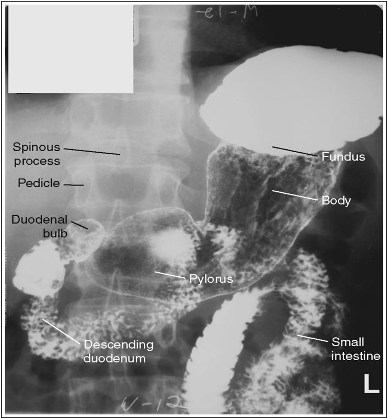

What position is this patient in?

LPO (Supine because barium is in the fundus, spine is not straight so they are rotated)